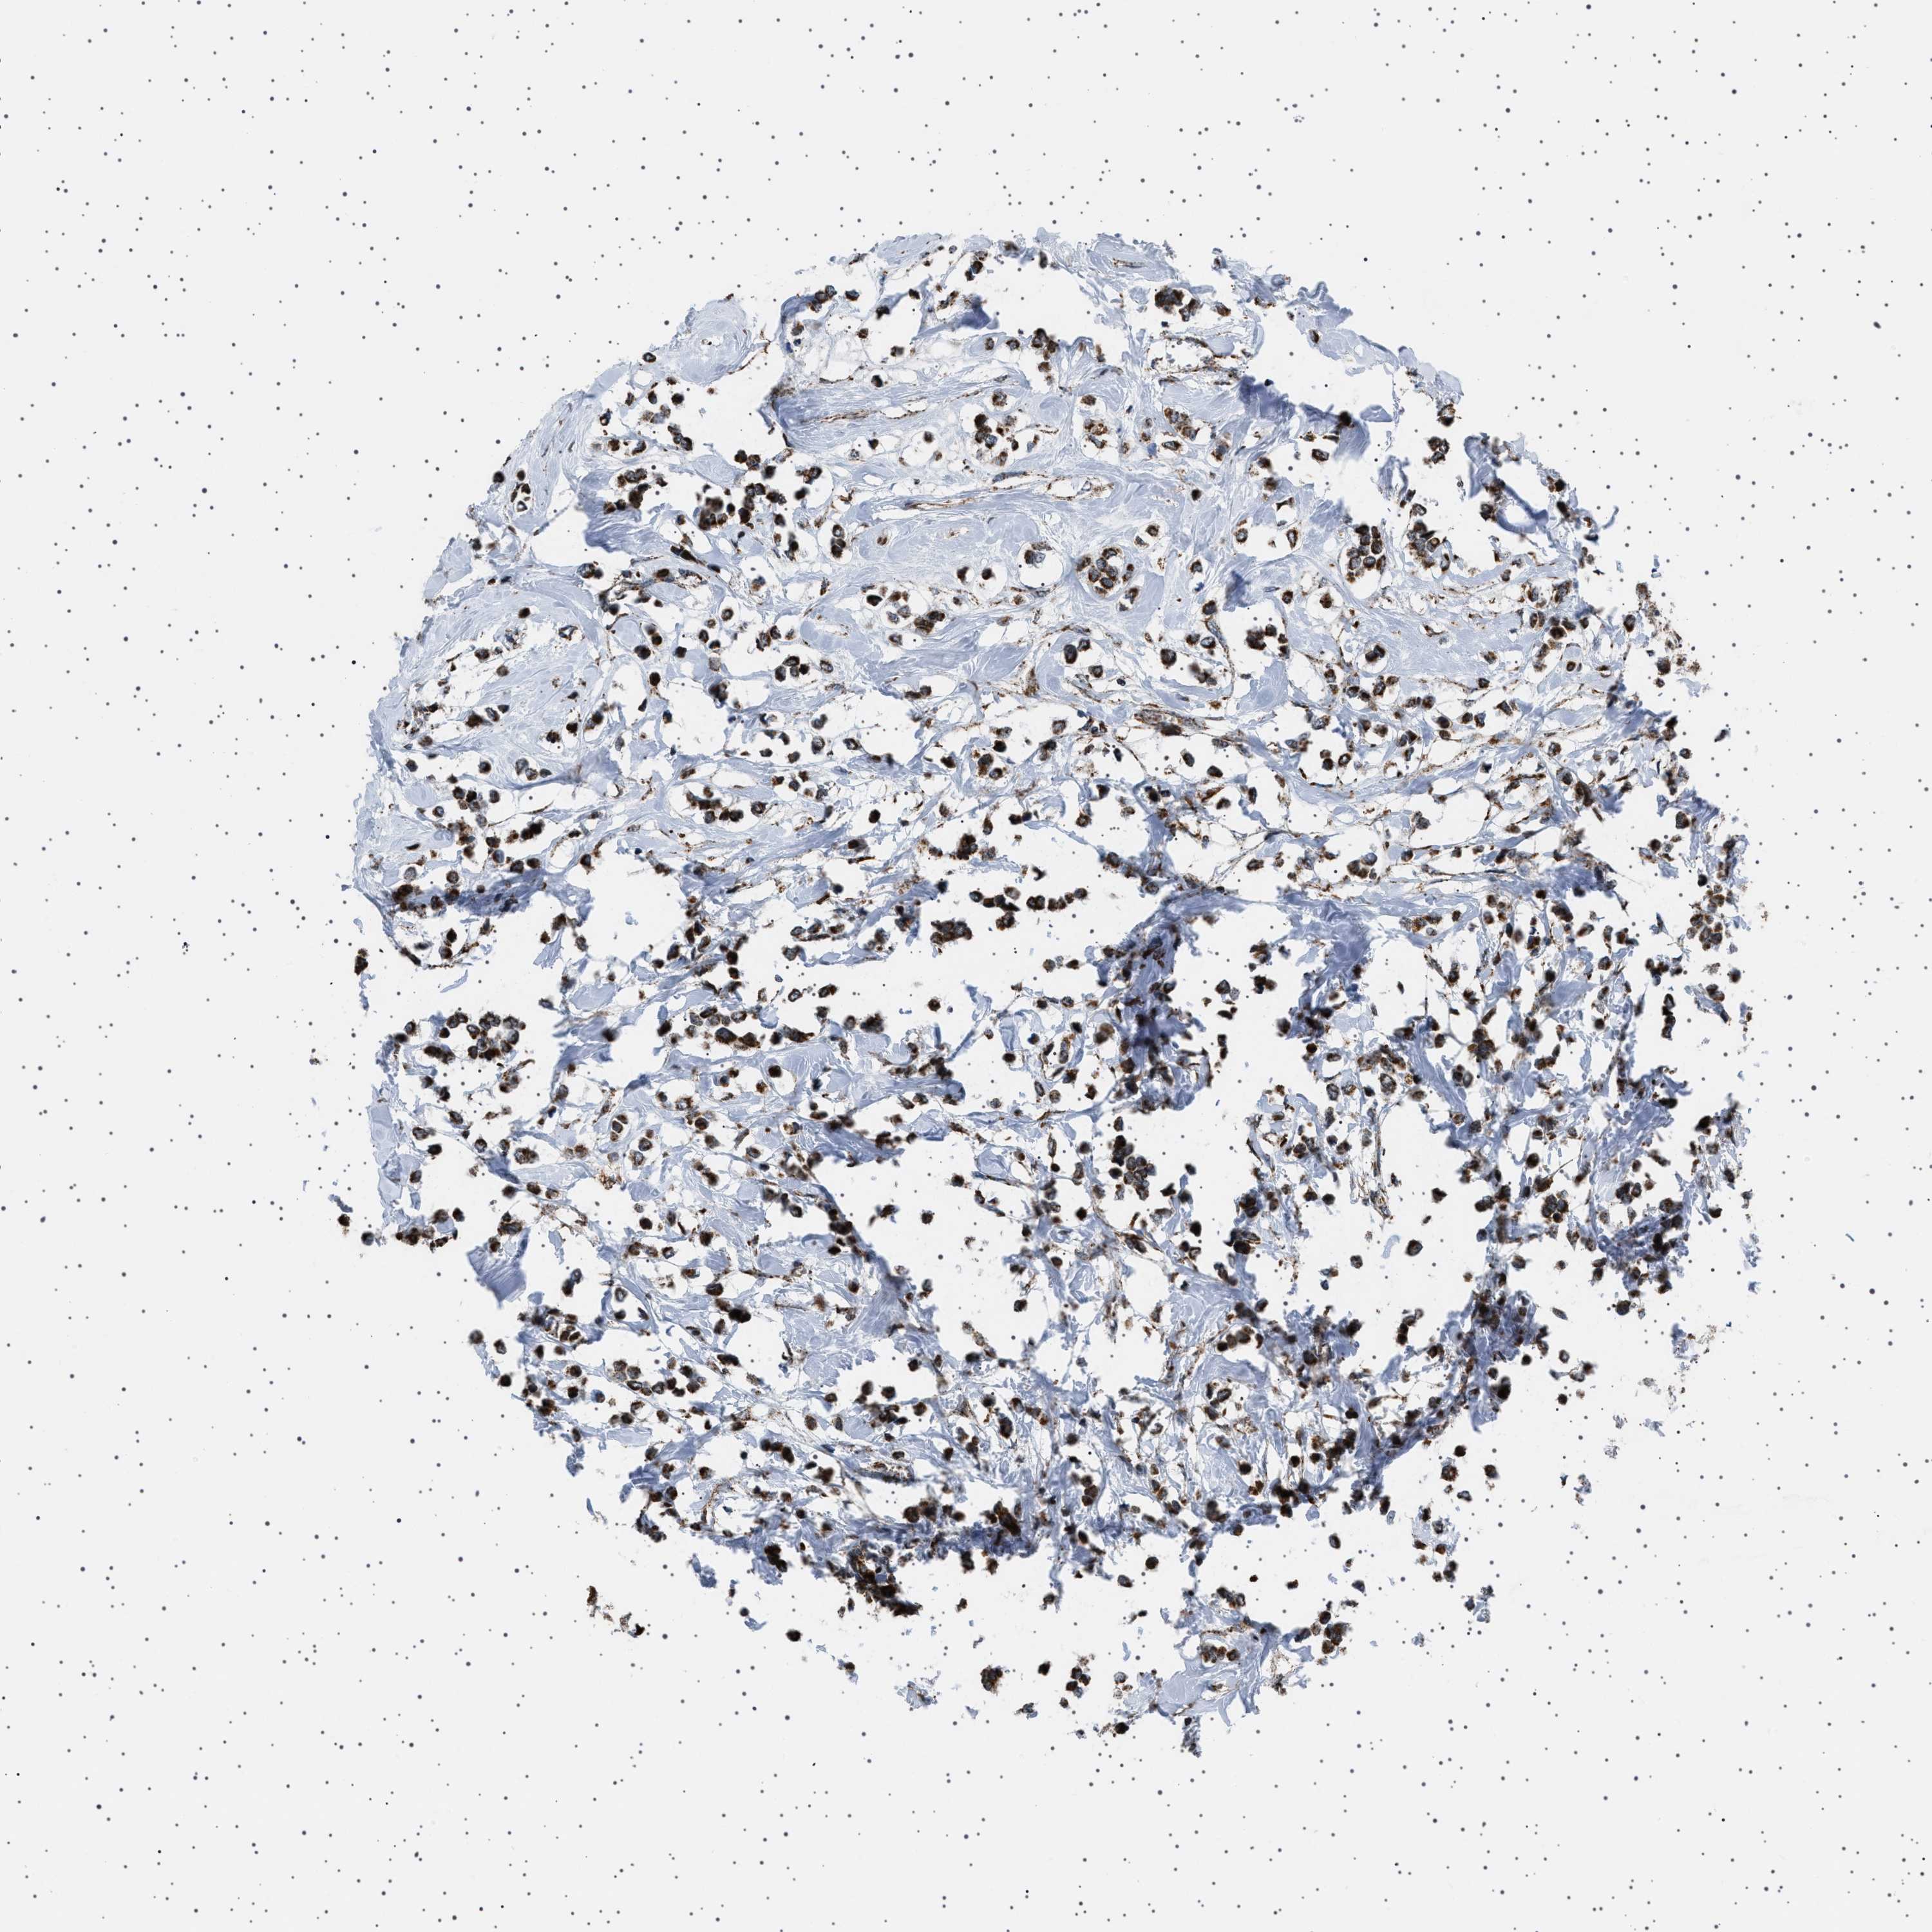

BRCA TCGA BRCA VALIDATION PROTEIN EXPRESSION

ANTIBODIES

AND

VALIDATION